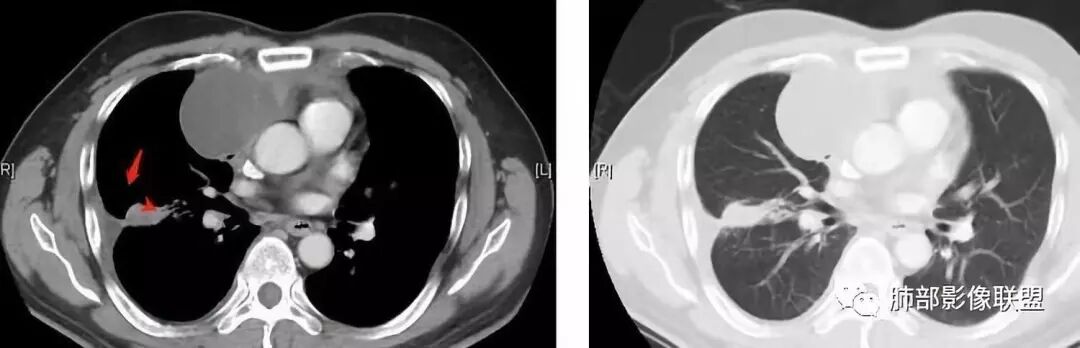

肺内结节,近端支气管堵塞狭窄

整体边缘收缩,部分膨隆

炎性要考虑,但恶性不能排除

1、右肺内病灶,病灶呈结节样,边缘欠规则,局部膨隆,叶间裂胸膜牵拉凹陷,再看相应支气管腔堵塞截断,临床资料胸水中查到癌细胞,均提示病灶倾向恶性,腺癌的病理意见与之相吻合。

黄勇老师总结,腺癌如果与胸膜、叶间裂紧贴或伴胸膜凹陷,胸膜、叶间裂多发结节,应当高度怀疑腺癌转移。